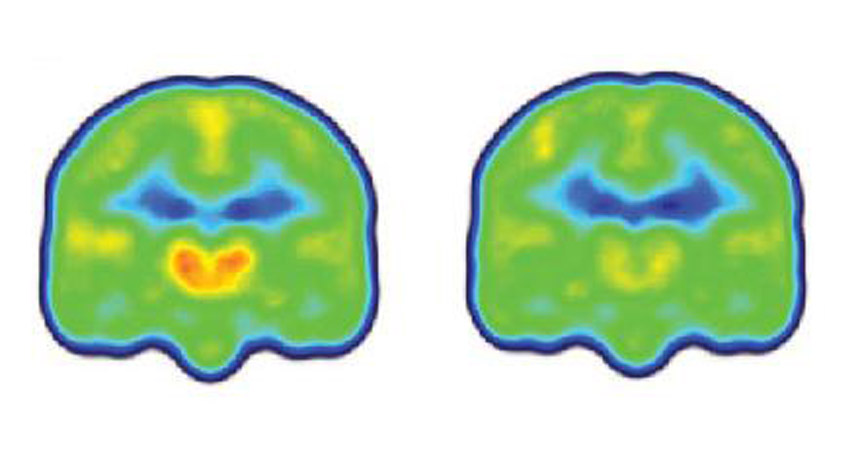

SEEING PAIN People with chronic pain (left) have higher levels of a protein linked with inflammation (orange and red) in their brains than people without chronic pain (right), a finding that could help improve treatments for the condition.

MARCO LOGGIA, MASSACHUSETTS GENERAL HOSPITAL